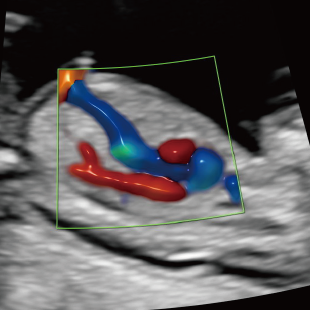

赤ちゃんの3~5%は、何らかの病気や医学的な介入を要する状態をもって生まれてくるといわれており、その中には、妊娠中・出生時・出生後に緊急の対応を要するものも含まれます。 特に先天性心疾患は比較的頻度が高く、約100人に1人の赤ちゃんが先天性心疾患を合併し、重症度や緊急性の高い症例(生後に入院や手術が必要な症例)は約1000人に4人といわれています。

Voluson Expert 22®(GEHealthcare)という産婦人科領域におけるハイエンド超音波診断装置を使用しています。 従来機種と比べ、より高精細な画像描出性能と高度な解析機能を備えており、 胎児の発育や形態をより詳細に観察することが可能です。